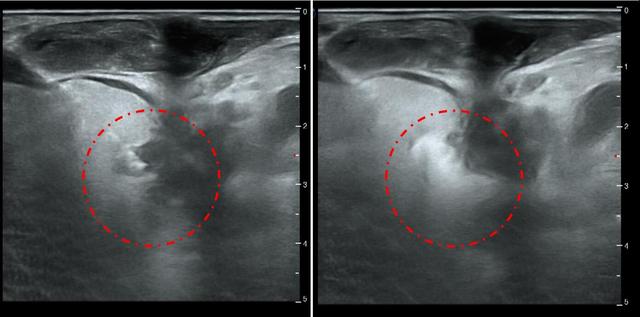

治疗前甲状腺旁腺素非常高(3300pg/ml),血钙正常,超声显示双侧甲状腺旁腺明显增大(如下图),核素扫描显示甲状旁腺功能亢进性骨代谢异常性骨病(骨骼变形)。

介入微创消融治疗时,将功能亢进的甲状旁腺原位灭活(如下图)